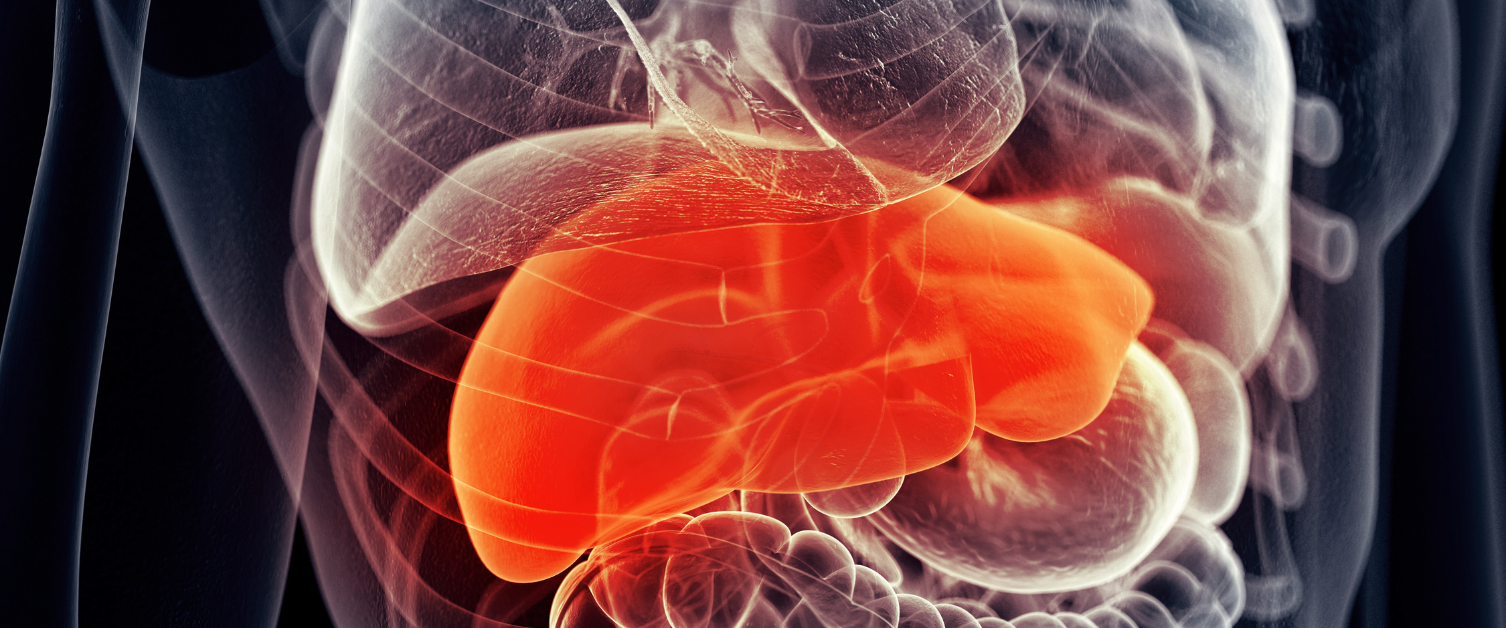

Clefyd yr iau brasterog di-alcohol

Clefyd yr iau brasterog di-alcohol yw’r term a ddefnyddir am amrywiaeth o gyflyrau a achosir gan groniad o fraster yn yr iau. Fel arfer, gwelir hyn mewn cleifion sydd dros eu pwysau neu sy’n ordew.

Nid yw clefyd yr iau brasterog di-alcohol fel arfer yn achosi unrhyw niwed yn y cyfnod cynnar, ond gall arwain at niwed difrifol i’r iau, gan gynnwys sirosis, os bydd yn gwaethygu.

Mae bod â lefelau uchel o fraster yn eich iau hefyd yn gysylltiedig â risg gynyddol o broblemau iechyd difrifol, er enghraifft diabetes, pwysedd gwaed uchel a chlefyd yr arennau.

Os oes gennych ddiabetes eisoes, mae clefyd yr iau brasterog di-alcohol yn cynyddu eich siawns o ddatblygu problemau â’r galon.

Os caiff ei ganfod yn gynnar a’i reoli yn gynnar, mae’n bosibl atal y clefyd rhag gwaethygu a lleihau faint o fraster sydd yn eich iau.